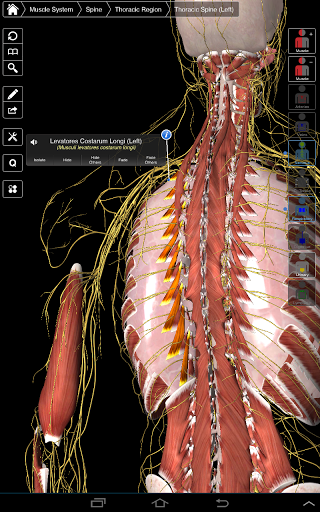

Essential Anatomy 3 represents the latest in groundbreaking 3D technology and innovative design. A cutting edge 3D graphics engine, custom built by 3D4Medical from the ground up, powers a highly-detailed anatomical model and delivers outstanding quality graphics that no other competitor can achieve.

The app represents a unique approach to learning general anatomy. The graphics are unparalleled and make learning, through the use of informative content and innovative features, a rich and engaging experience.

⁃Muscles

⁃Nerves

Essential Anatomy 3 is responsive, visually stunning and effortless. The app is fully 3D, meaning that you can view any anatomic structure in isolation, as well as from any angle.

Clever functionality found within the app allows the user to strip away layers of muscle via the ‘scalpel’ tool. This app provides users with the ability to turn on/off systems without the need to deselect individual structures or muddle through a multitude of predefined regional tabs, like other apps.

---- Over 4,000 highly detailed anatomical structures

---- Latin nomenclature for each anatomical structure